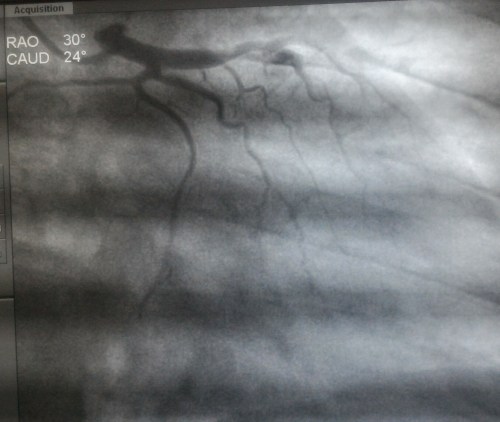

Now , have a look at this , its a rare example of how a left main might Ignore the rule of bifurcation just like that !

Left main simply continues as left main* after giving off a casual side branch from mid left main shaft .Yes , Its a innocuous looking LCX which would be non dominant as expected

LCX arises exactly mid way in left main , (Technically LAD begins at this point ) but , can you find any difference in the left main after giving off LCX branch.

Can we say left main continues as LAD without a bifurcation ?

Or shall we say left main gives off a premature early side branch ( true LCX) non bifurcating branch ?

It is an unusual anatomy and as expected , this patient had a dominant RCA .